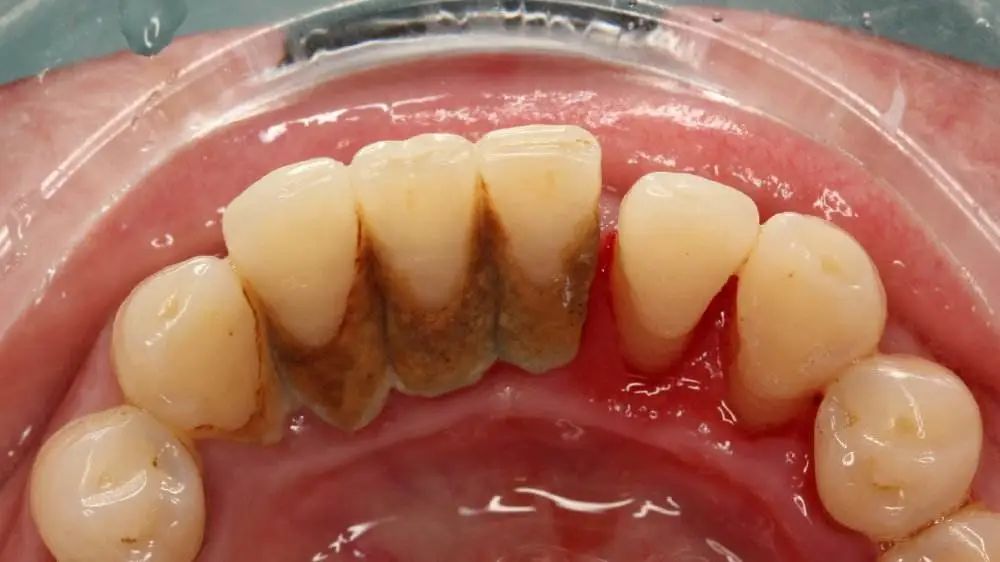

通常来说,导致牙龈出血的主要因素就是牙结石堆积过多,刺激牙龈产生了炎症反应,因此牙龈出现了红肿出血的情况。

如果不及时处理,牙结石越来越多,加上细菌毒素导致牙周组织发炎,还会出现牙龈脓肿、牙槽骨吸收,最后导致牙齿松动,甚至脱落。因此,这个时候就需要及时找牙医解决问题了。

一般情况,如果是早期的牙龈炎可以通过洗牙的方式改善牙龈出血的症状。洗牙就是通过超声波震动去除牙齿表面的牙结石,包括洁治、喷砂、抛光三个步骤,可有效改善早期牙龈炎症状。

不过,一些没有及时治疗的牙龈炎患者,通常前来治疗时牙龈炎症已经朝着牙齿根部发展,形成了牙周袋,牙结石和细菌毒素在牙周袋内,时间长了会引起牙周组织(牙槽骨)的炎症和吸收,最后导致牙齿松动。

因此,这个时候光是龈上洁治(洗牙)已经不能够解决根本问题,牙医通常建议进行洁治+龈下刮治,也就是不仅要去除牙齿表面的牙结石,还要去除牙周袋的细菌,给牙周组织的愈合提供一个有利的环境。